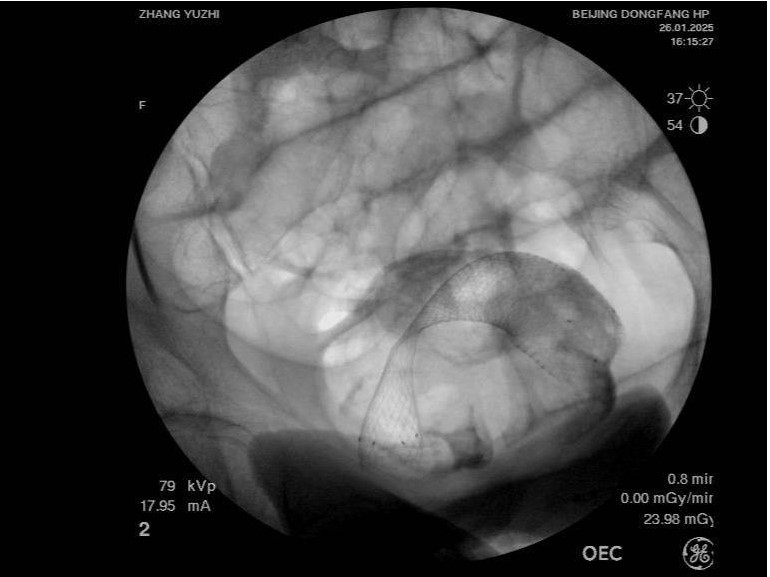

治療前腹CT示腸腔明顯擴張 治療后立位腹平片示腸道梗阻較前明顯緩解